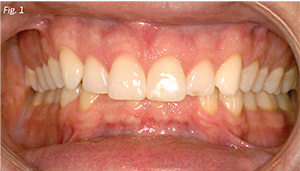

Although orthodontic treatment, especially when combined with orthognathic surgery, can create dramatic changes in the vertical dimension, we must first determine what is necessary in order to achieve our treatment objectives. Although some patients are overclosed and need to have their vertical dimension increased (Fig. 1), many times the diagnosis and resulting treatment plan are inappropriate. The wrong teeth might be intruded or the entire posterior vertical dimension might be inappropriately increased through posterior restorations. In other cases, posterior restorations are indicated. Proper diagnosis and treatment planning are critical to the long-term success of these cases.